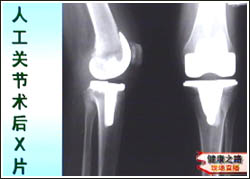

主持人:更严重的情况是不是就只能做人工关节置换术了? 邱贵兴:在年龄偏大、关节持续疼痛并活动受限、X光关节明显破坏的情况下,就应该考虑关节置换了。关节置换其实是一项很成熟的技术,早在20世纪30年代就已经出现了,最多的就是髋关节和膝关节的置换,美国每年进行髋关节和膝关节置换的患者各30万例,而在我国一亿三千万老人中进行膝关节置换的人数还不到一万。原因是我国的普及教育不够。来看一张图,关节置换实际上就是把关节表面的一层不平的部分去掉,换上一个很光滑的人工关节,这样症状可以明显改善。

主持人:人工关节置换的费用是多少? 翁习生:一般来讲如果是用进口的人工关节全部费用(住院费、医疗费、材料费)大约在4.5万元到5.5万元左右。